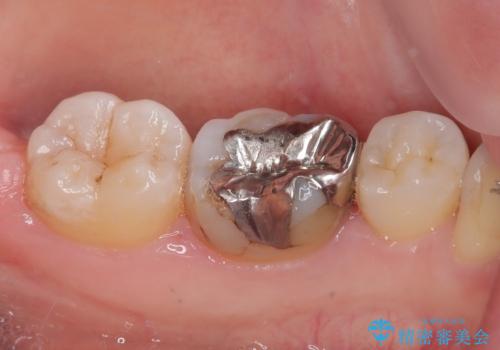

- 左下の銀歯のところがしみるとのことで来院された患者様です。

レントゲン上で金属の詰め物(メタルインレー)の下に虫歯を認めました。

拡大鏡視野下で、金属の詰め物(メタルインレー)、虫歯の除去を行い、オールセラミッククラウンに適した形に整えました。